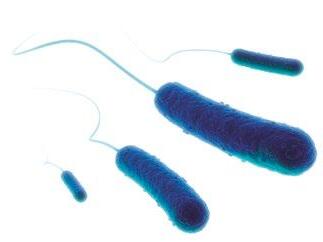

They are secondary metabolites of certain fungi (genera Aspergillus, Penicillium, Fusarium, Alternaria, and Claviceps)[1] and are produced before harvest of grains (fungi as plant pathogens), or during storage (fungi growing saprophytically).

AFs are produced mainly by Aspergillus flavus, A. parasiticus and A. nomius and are detected usually in maize, peanuts and cottonseed.

On the other hand, DON as a member of the trichothecene B group, is produced by Fusarium fungi which are one of the most important phytopathogenic fungal genera groups. That group is also responsible for the production of ZEN and FBs[15]

The fumonisins are a family of toxins produced mainly by Fusarium verticillioides and F. proliferatum, with FB1 and FB2 as the most frequently observed, whereas FB1 represents approximately 70% of the natural contamination of maize[38]

Aspergillus species mainly, and Penicillium species can produce ochratoxins with OTA having major nephrotoxic properties.